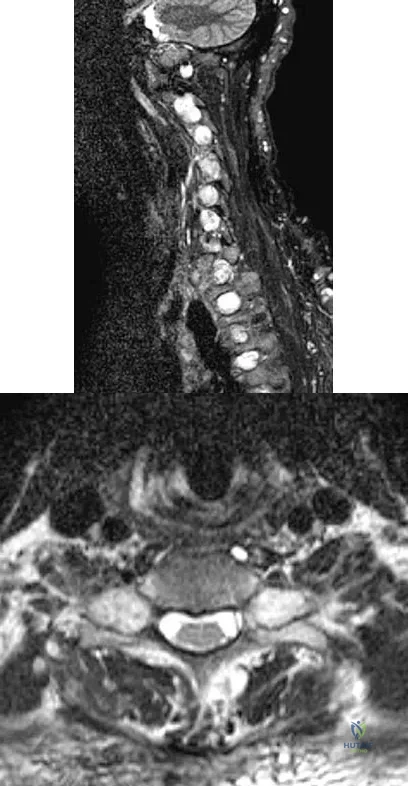

A 32-year-old man notes increasing back pain and progressive paraparesis over the past few weeks. He is febrile, and laboratory studies show a WBC of 12,500/mm3. MRI scans are shown in Figures 6a and 6b. Management should consist of

Explanation